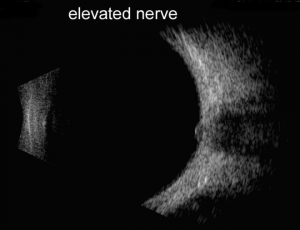

Papilledema vs. pseudopapilledema

Papilledema is optic nerve head swelling secondary to increased intracranial pressure and pseudopapilledema is elevation of the optic nerve head secondary to buried optic nerve head drusen or anomalous optic nerves. In a 2014 study of 87 patients by Carter et al., orbital ultrasonography had 90% sensitivity and 79% specificity for papilledema, compared to 90% and 67% respectively via lumbar puncture[2]. This is further supported by the 2018 study by Saenz et al reporting 91.3% sensitivity at 95% specificity for diagnosis of papilledema via A-scan ultrasound to measure optic nerve sheath diameter (ONSD) and perform the 30° test, compared to only 56.5% sensitivity using RNFL thickness measurement obtained via spectral-domain OCT[3]. A positive 30° sign is a reduction in ONSD by > 20% from primary gaze to 30° gaze, suggestive of the redistribution of fluid and increased intracranial pressure.

In a study comparing ultrasonography to magnetic resonance imaging (MRI) of the orbit, using a cutoff of ONSD >4.8mm in ultrasound had a sensitivity and specific of 77% and 82%, respectively, which was very comparable to MRI sensitivity and specificity of 77% and 83%, respectively using a cutoff of OSND > 6.0mm[4]. (See related: Papilledema and Pseudopapilledema). Wang et al. evaluated a cohort of 60 patients with suspected elevated intracranial pressure (ICP) found ONSD was strongly correlated with ICP, as was the subsequent decrease in ONSD and ICP on serial follow-up[5] .